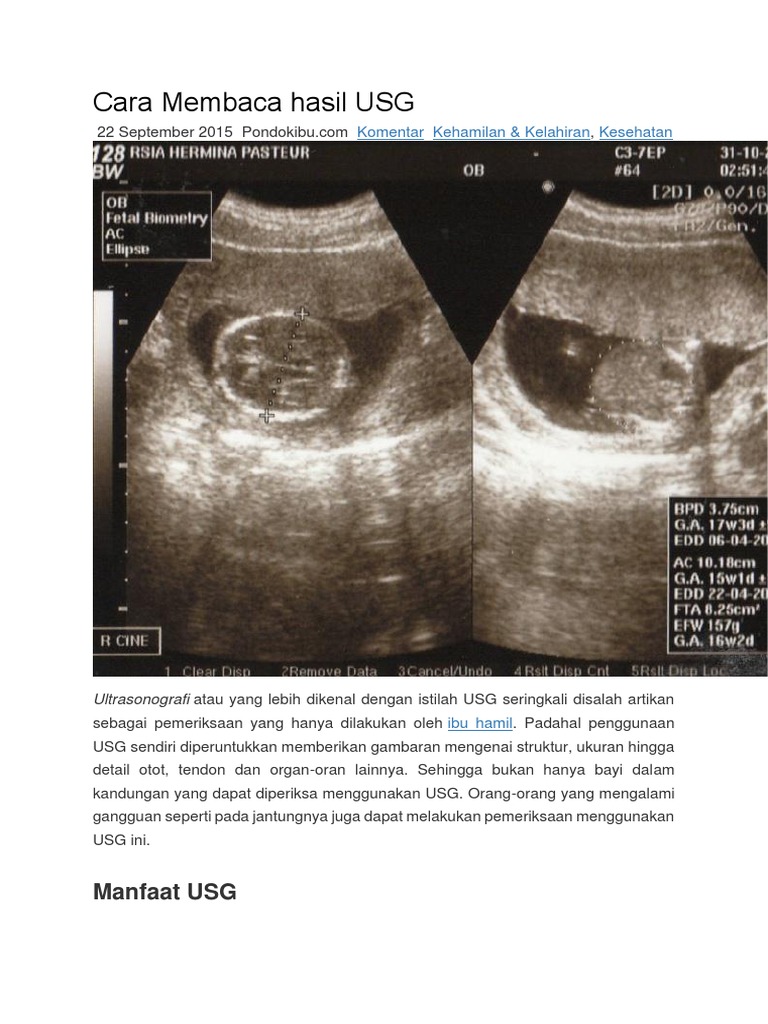

Ketika anda mencetak hasil pemeriksaan usg anda mungkin akan menemukan beberapa singkatan yang diambil dari bahasa inggris. Foto usg terdiri dari beberapa tabel atau angka angka yang diukur dari pengukuran dokter terhadap tungkai lengan kaki dan diameter kepala. Sebagai contoh jika rahim anda diperiksa dengan ultrasonografi. Ga gestational age. Beberapa istilah yang umum ada di hasil foto usg antara lain. Pada dasarnya pemeriksaan usg ditujukan untuk mengetahui usia panjang dan berat janin serta estimasi waktu kelahiran.